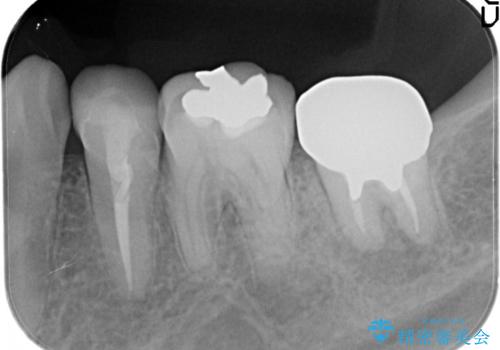

- 奥歯が痛いことを主訴に来院されました。

レントゲンにて根尖病変を認め、根管治療を行ったのちセラミッククラウンにて修復しました。根管治療は川島先生に依頼。